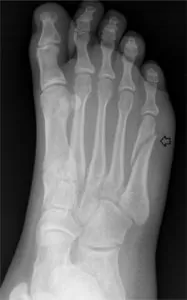

9. Stress Fractures

Metatarsals, tibia, sesamoids, and lumbar spine

- What it is: Stress fractures are small fractures that happen in your bones in response to TOO MUCH load. The bones are unable to keep up with the recovery process between sessions and can start to have micro-breaks in the bone.

- Common Symptoms: Pain in the area of the stress fractures which feels worse with loading, and feels better if rested.

- Treatment: Rest the area to allow the bone to heal (avoid high impact movements), and then initiate progressive loading to get the area to tolerate your practices again. This may take 1-2 months to get better.

- Prevention Tips: Load appropriately – beware of sudden changes of your activity level in terms of frequency, duration, or intensity of your routines. Ensure you are eating well – proper nutrition is important in your body’s recovery process.